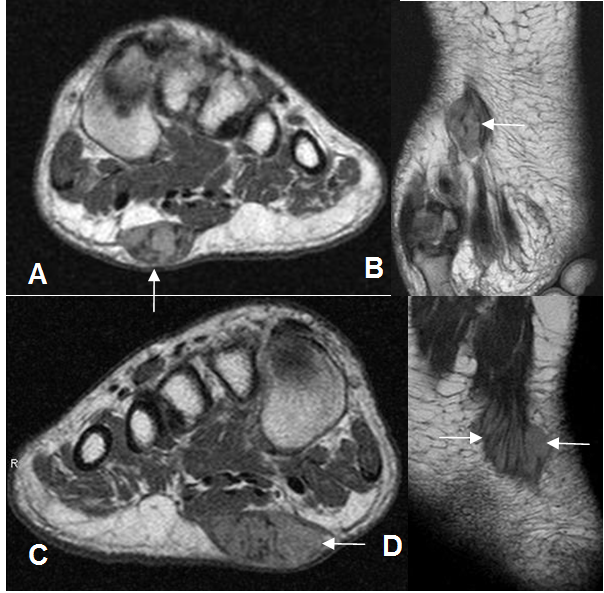

Fig 113 A. Fibromatosis plantar.

A: RM coronal y B: RM axial en T1 con contraste. Imagen ovalada, la cual realza con el contraste, que compromete el ramo del 2º dedo de la fascia plantar y corresponde a fibromatosis.

C: RM coronal y D: RM axial con contraste. Igual paciente anterior con lesión en el otro pie, que compromete los ramos faciales del 1º, 2º y 3º dedo, por fibromatosis.

Fig 113 B. Fibromatosis plantar gigante.

A: RM sagital en T2. Imagen ovalada en la planta del pie, hipointensa en T2, por la presencia de tejido fibroso.

B: RM sagital en T1 simple y C: RM T1 con contraste. Lesión hipointensa, que realza fuertemente con el contraste.